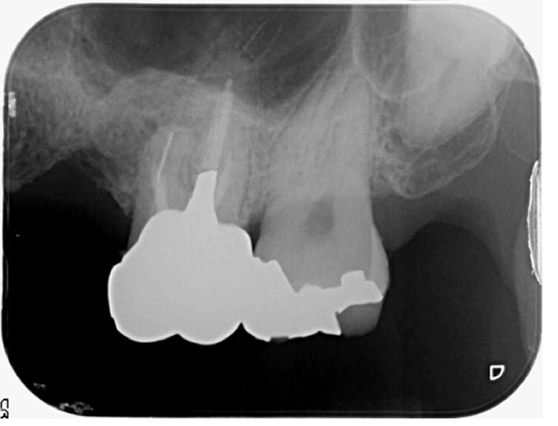

根管治療 症例4

抜歯と言われたが、抜歯する必要があるか診てほしい

破折ファイルの残存を認めるが抜歯と診断する所見がなかったため根管治療を提案。

根管治療で破折ファイルを除去。経過観察2年で良好な経過と治癒を確認